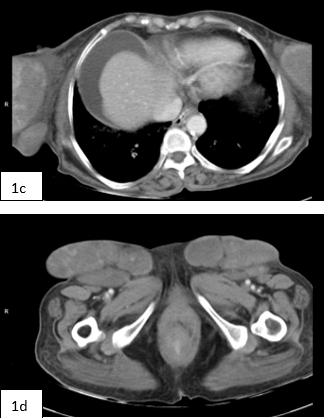

Fig 1a: Ultrasound shows coarse heterogenous liver parenchyma with surface irregularity & nodularity Fig 1b,c,d : CECT Imaging shows Small nodular cirrhotic liver with multi lobulated , well defined masses having mild heterogeneous post-contrast enhancement & few calcific foci in bilateral axilla and inguinal region. Hugely enlarged breasts partly seen in the scan. Ascites present. Fig 2 : 2D mammo (a,b) and Tomo images (c,d) of both breasts show bilateral high density large masses with smooth margins and no architectural distortion however few course heterogenous calcifications present randomly in breast parenchyma. (compromised scan quality is attributed to massive breast size) Fig 3 a,b,c,d : Ultrasound of bilateral breasts show iso to heteroechoic large breast masses occupying almost entire breasts. Normal breast tissue was compressed and difficult to identify. Colour doppler demonstrates significant vascularity within the masses. Fig 4 : Ultrasound of axillary lymph nodes. Fig 5 a,b : Biopsy from breast masses showed amyloid deposits (pink) predominantly around the ducts and blood vessels (a), demonstrated well on congo red stain (b).